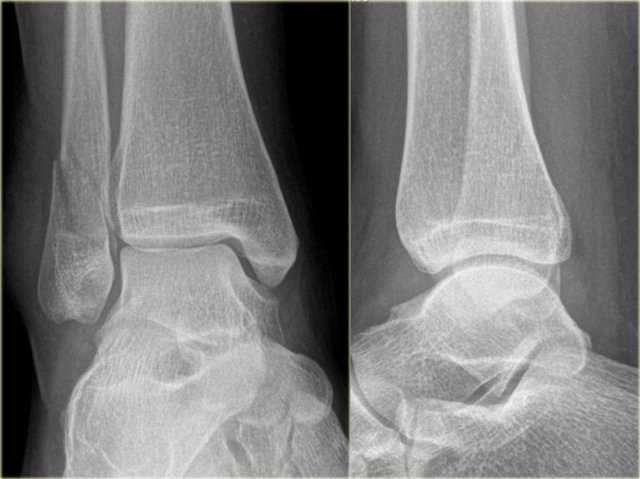

Weber B fracture Weber B fracture

The radiographs show a typical Weber B fracture.

First study the images and then continue reading.

Do you see what stage this is?

This is a Weber B stage 4 injury.

Notice that all 4 stages are visible:

1. Rupture of the anterior syndesmosis - seen as widening of the space between the distal tibia and fibula (lateral clear space).

2. Oblique fibula fracture at the level of the syndesmosis - i.e. Weber B fracture.

3. Tertius fracture - seen on AP view (red arrow) and on lateral view (yellow arrow).

4. Rupture of the medial collateral ligaments - seen as widening of the space between the medial malleolus and the talus (medial clear space)